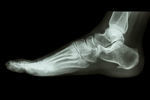

シーバー病・踵骨骨端症

【実例】シーバー病